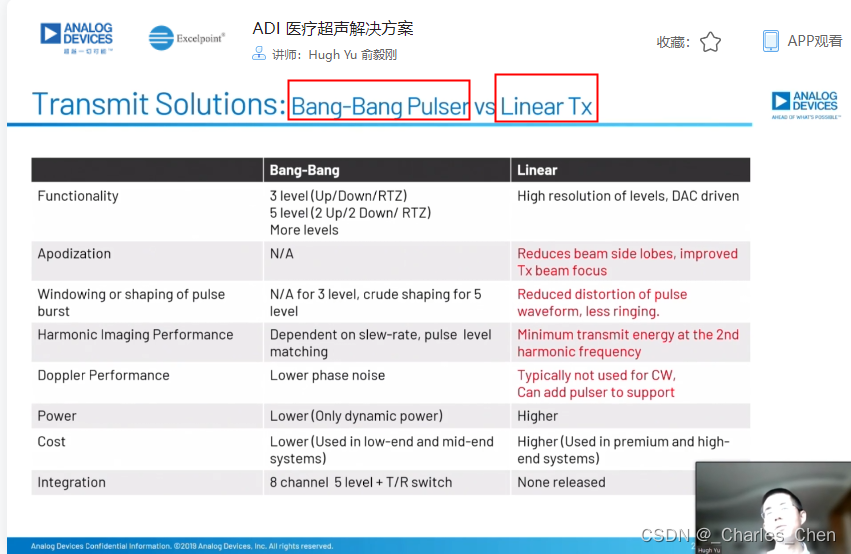

数字发射波束成形器用于产生所要求的数字发射信号,以正确的时间和相位生成聚焦发射信号。高性能超声系统可通过任意波形发生器产生复杂的发射波形,从而优化图像质量。这些情况下,发射波束成形器以大约40MHz速率生成8位至10位数字字符,并以此产生所要求的发射波形。数/模转换器(DAC)将数字波形转换成模拟信号,通过线性高压放大器进行放大,用于驱动传感器单元。由于这种发射技术占用较大体积,而且价格昂贵、需要消耗较高能量,所以,这种架构只限于昂贵的非便携设备。多数超声系统并不使用这种发射波束成形技术,而是采用多级高压脉冲发生器产生需要发射的信号。在这种替代方案中,利用高集成度、高压脉冲发生器快速切换传感器单元至适当的可编程高压电源,产生发射波形。为了产生一个简单的两极发射波形,脉冲发生器需要交替地将传感器单元切换到由数字波束成形器控制的正、负发射电压。更复杂的设计可以让传感器单元切换至多路电源和地,从而产生更复杂、性能更好的多重波形。

近几年,随着二次谐波成像的广泛应用,高压脉冲发生器对于斜率和对称性的要求越来越高。二次谐波成像利用了人体的非线性声学特性。这些非线性特性倾向于将频率fo的声能转变成2fo频率。多种原因使得接收二次谐波信号能够获得更高的图像质量,因此,二次谐波成像得到了广泛应用。

二次谐波成像有两种基本的实现方法。一种称为标准谐波成像,尽可能抑制发射信号的二次谐波,从而使接收到的二次谐波主要源于人体的非线性。这种模式要求二次谐波的发射能量至少低于基波能量50dB。所以,发射脉冲的占空比要求是准确的50%且误差小于±0.2%。另一种方法称为脉冲反相,利用反相后的发射脉冲产生同一图像路径的相位相反的两路接收信号。在接收器中对这两路反相接收信号求和,恢复由于人体非线性产生的谐波信号。这种脉冲反相的方法必须在叠加时尽可能抵消发射脉冲的反相成分。所以,高压脉冲发生器的上升时间和下降时间必须严格一致。